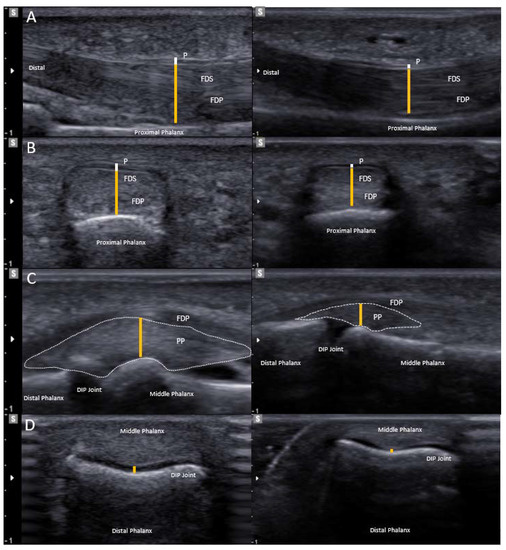

3.2. Clinical Investigation

3.4. Soft Tissue Adaptations

4.1. Soft Tissue Adaptation in the Fingers